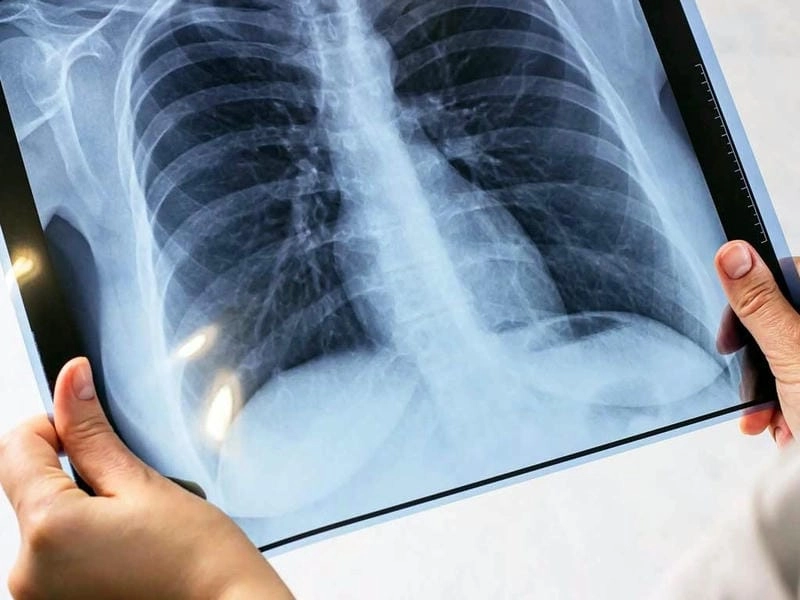

Cảnh báo: tổng hợp ảnh bệnh lao phổi chân thực này không dành cho người yếu tim. Đây là loạt hình ảnh y khoa được các chuyên gia sưu tầm và xác thực, ghi lại quá trình tiến triển của bệnh từ giai đoạn đầu đến giai đoạn nguy kịch. Từng mảng mô phổi bị ăn mòn, xơ hóa, hoại tử được phơi bày rõ nét dưới ánh sáng X-quang lạnh lùng. Những hình ảnh này không chỉ mang tính chất minh họa y học, mà còn là hồi chuông cảnh tỉnh cho bất kỳ ai còn lơ là với căn bệnh nguy hiểm này.